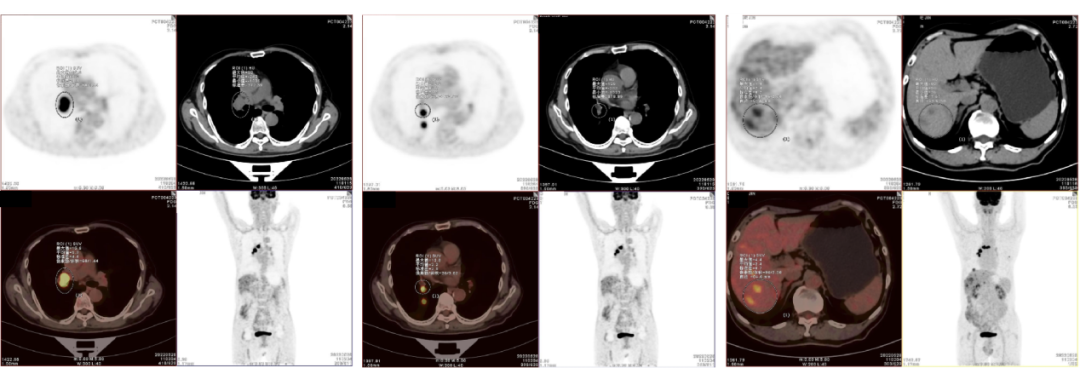

2022-5-28  PET-CT:1.右肺下叶背段支气管腔内一软组织结节,FDG代谢异常增高;右肺下叶背段胸膜下一略不规则结节影,FDG代谢轻度增高;纵隔气管前腔静脉后、主肺动脉窗、右肺门及右肺内支气管旁可见多发肿大淋巴结,FDG代谢异常增高;肝脏实质内多发稍低密度结节影,较大直径约1.5cm,FDG代谢增高;考虑右肺下叶背段肺癌伴右肺内、淋巴结及肝多发转移,小细胞肺癌可能大。2.两肺多发微小结节影,FDG代谢未见增高,考虑性结节可能大,部分合并转移不除外。3.两肺慢性炎症伴肺气肿,少许肺大泡形成,两侧部分胸膜增厚、粘连。

影像学检查图像